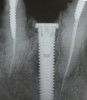

Subsequently, Trisi et al2 confirmed that increased insertion torque reduced implant micromotion when the implants were subjected to lateral forces in vitro (bovine bone). However, it was noted that this relationship may not always be true for all implant designs (Figure 3) and drilling techniques.61 For instance, compared with soft bone, there may be no benefit in increasing insertion torque in dense bone after stability is attained. One can surmise that a moderate increase of insertion torque may provide some benefits with respect to reducing micromotion, especially in less dense bone. However, the amount of increased force that is beneficial is unclear. Another technique to enhance initial stability is to use tapered implants, which develop elevated insertion torque forces. 14,62

Fig 3. Examples of implants with different thread designs. On the left is an implant with standard v-threads, and on the right is an implant with larger, more aggressive threads. The implant on the right was inserted with 20-Ncm-greater insertion torque than its counterpart.

Figure 3